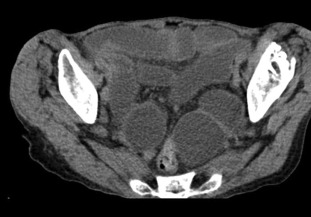

Abdominal X-ray examination showed dilatation of small bowel loops in entire abdomen. CT scan demonstrated dilated bowel loops (Figure 1) and incarcerated bowel between the external obturator and pectineal muscles (Figure 2), suggestive of bowel obstruction secondary to incarcerated obturator hernia. Four of the obturator hernias were in the left and the other two in the right.

Incarcerated small bowel between the external obturator and pectineal muscles ...

Figure 2.

Incarcerated small bowel between the external obturator and pectineal muscles (arrow).